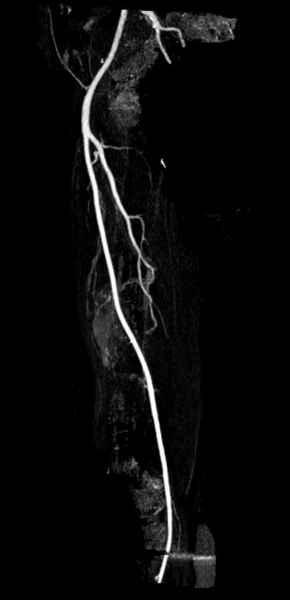

Со слов, больная ничем не болела, только последние 3 месяцев чувствовала боли в бедренной области. КТ брюшной полости подтвердил увеличенную правую почку. (5-6)

Для предупреждения кровотечения во время рассверливания, за день до операции провели эмболизацию сосудов питающий метастаз. http://radiology.rsnajnls.org/cgi/reprint/150/3/673.pdf (7-11, 12-15-16)